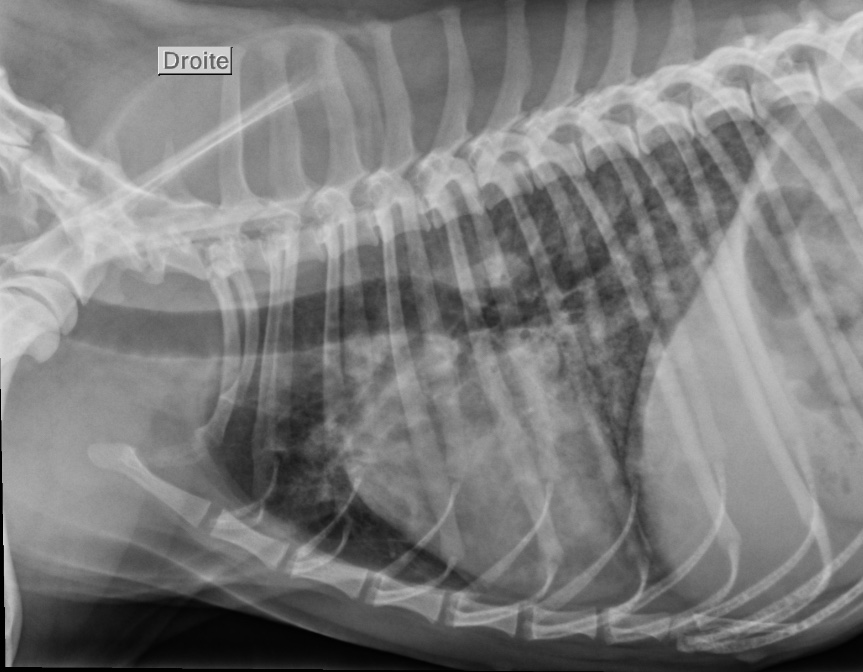

Des radiographies du thorax sont réalisées (figures 1 et 2).

1 . Interprétez les radiographies du thorax – Quels sont les hypothèses diagnostiques à envisager au vu de ces radiographies ?

Au niveau des structures extra thoraciques, nous observons un contenu aérique dans l’estomac.

Au niveau des structures intrathoraciques, nous notons aucune anomalie au niveau de l’espace pleural, du médiastin et au niveau des structures cardiovasculaires (indice de Buchanan à 9,6). Au niveau du parenchyme pulmonaire, nous observons une opacification interstitielle diffuse sévère et plus marquée aux lobes caudaux dorsaux. Des zones multifocales d’opacifications alvéolaires sont observées et masquent par endroits la silhouette cardiaque (figure 3).

Figure 3 : Radiographie du thorax vue de profil droit légendée

L’affection est localisée aux voies respiratoires profondes (bronches, bronchioles, alvéoles, parenchyme pulmonaire). L’œdème aigu du poumon cardiogénique est exclu par une auscultation cardiaque sans anomalie et des structures cardio-vasculaires normales aux radiographies. Le chien est jeune et ne fait pas parti des races prédisposées pour les causes inflammatoires (bronchite éosinophilique…), dégénératives et néoplasiques. L’œdème aigu du poumon non cardiogénique, des coagulopathies et des causes traumatiques semblent moins probables du fait de la chronicité des évènements. Le contexte anamnestico-clinique nous oriente donc vers une pneumonie infectieuse.